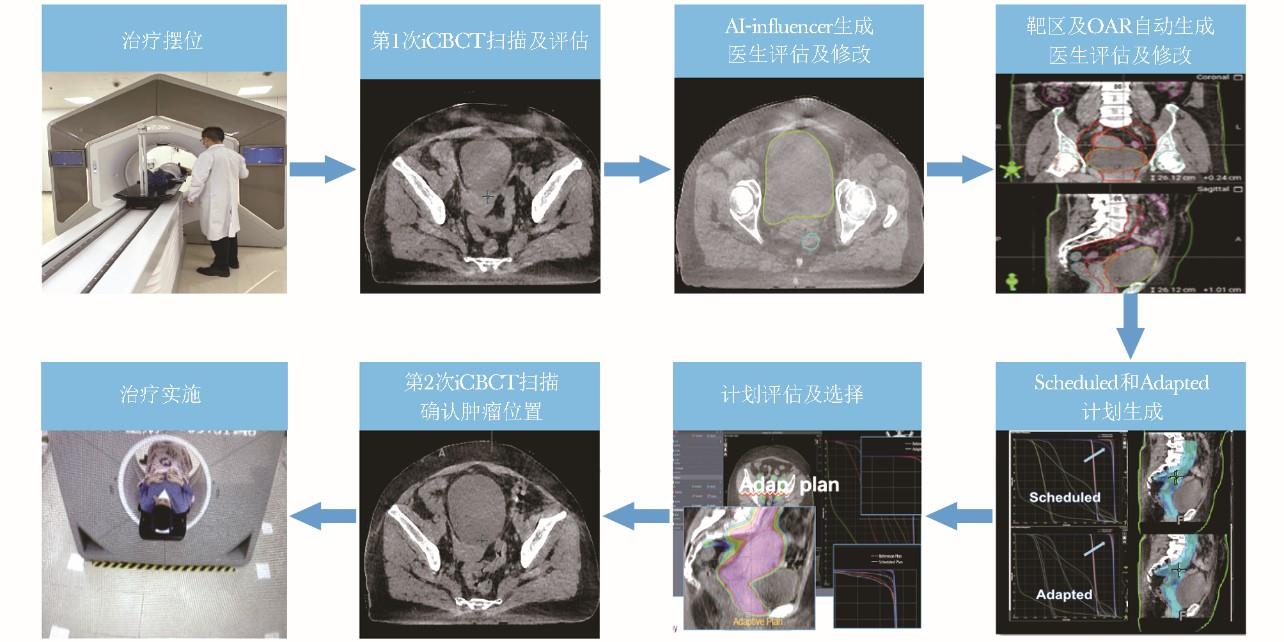

经医患双方充分地沟通及讨论,最终确定丽屏的放疗方案使用“基于迭代锥形束CT(iCBCT)的在线自适应放疗,采用9野均分固定野调强放疗(IMRT)技术。”

它是通过每次治疗前的高清图像引导技术(IGRT),评估患者的器官解剖和生理变化,或治疗过程中的反馈信息如肿瘤的解剖位置及大小,分析分次放疗与初始放疗计划设计间的差异,根据当下的变化对治疗方案每次实时做出调整。

在线自适应放疗在这方面具有很多明显的优势。在线自适应放疗可解决治疗过程中肿瘤位置和形状变化问题,特别适合每个分次间肿瘤自身或受周围正常器官位移影响变化大的病例;且与离线自适应相比,患者在放疗分次内无需离开治疗床,对治疗前扫描图像能重新快速制定治疗方案并实施,从而能够实现每次肿瘤精准放疗,既提高靶区照射准度,同时更好地保护肿瘤周围的正常组织。

在线自适应放疗整体治疗流程

丽屏记不住这项技术手段的名字和原理,但她知道这项技术能给她带来的好处。每次她只需要躺在治疗床上20多分钟,机器会对治疗前扫描图像重新快速制定治疗方案并进行精准放疗,并会极大程度上保护其他正常组织。